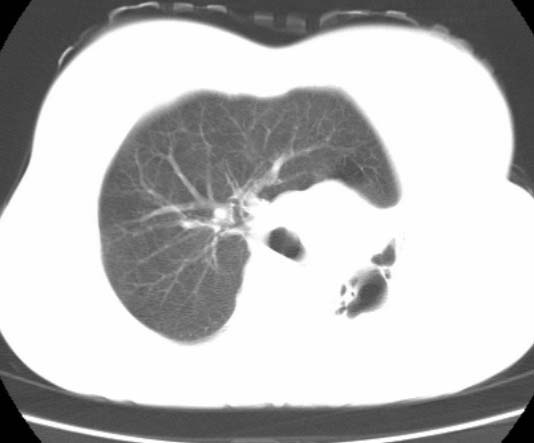

标题: CT25648:求教:是肺发育不全还是结核?

女  20岁。一月前咳血,诊“肺结核”抗痨治疗一月后,咳血停止,现复查。病人精神好。前后ct片对比未见明显变化。既往体检“正常”

1)考虑左肺结核并肺不张、支气管扩张。2)纵隔疝。

以前体检正常只能考虑左肺结核并肺不张、支气管扩张。2)纵隔疝。

考虑左肺结核,左肺毁损,纵膈左偏,既往体检正常不可靠,tb一个月也不会这个样子的,有钙化,应该病程较长,冰冻三尺非一日之寒!